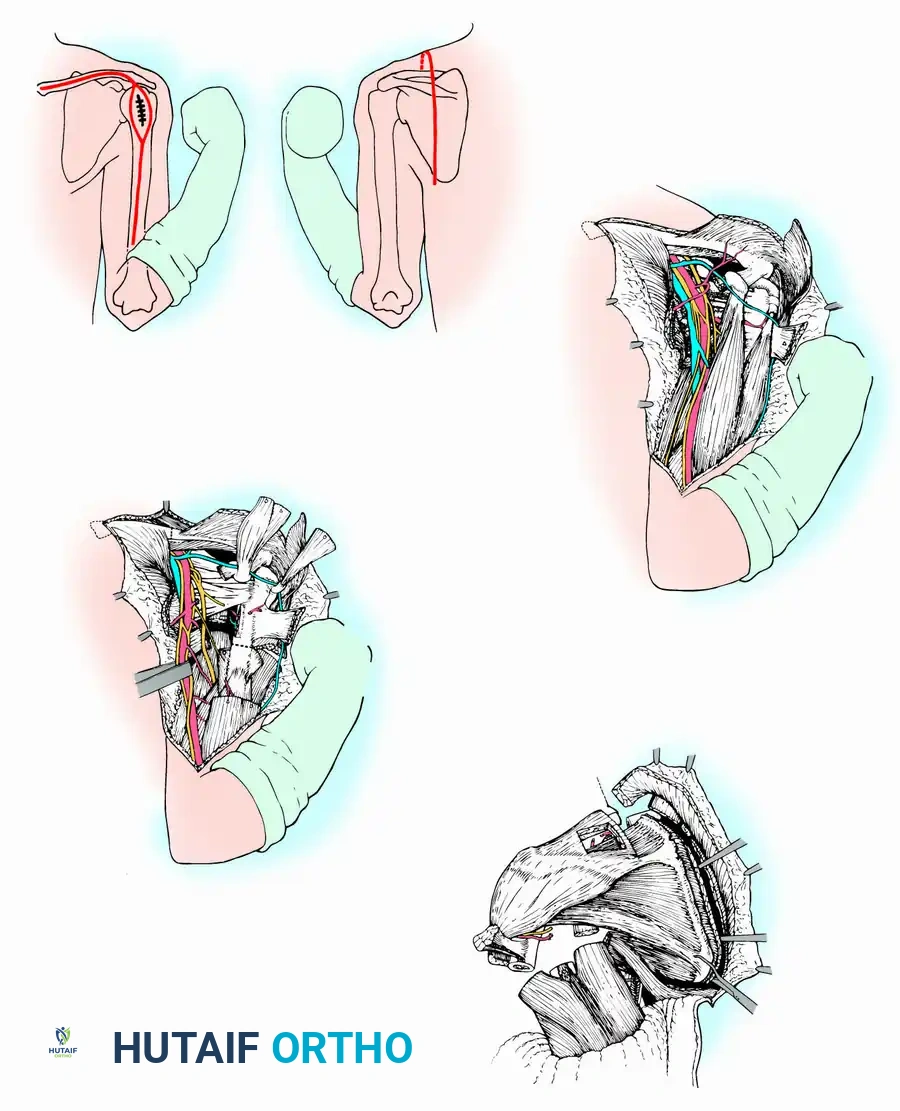

The Repiphysis Lengthening Procedure

The lengthening process is meticulously controlled:

1. The locking mechanism is located via palpation or fluoroscopy.

2. The patient’s limb is marked at the exact site of the internal mechanism.

3. An electromagnetic coil is placed circumferentially around the limb at the marked level.

4. The device is activated, generating a field that releases the internal spring.

5. Pre-expansion and post-expansion radiographs are obtained to quantify the exact lengthening achieved.